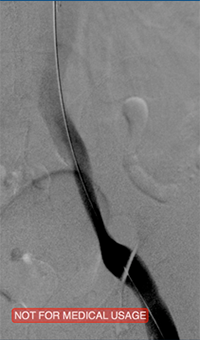

xray image of Iliac vein post-ZelanteDVT.

Iliac vein post-ZelanteDVT